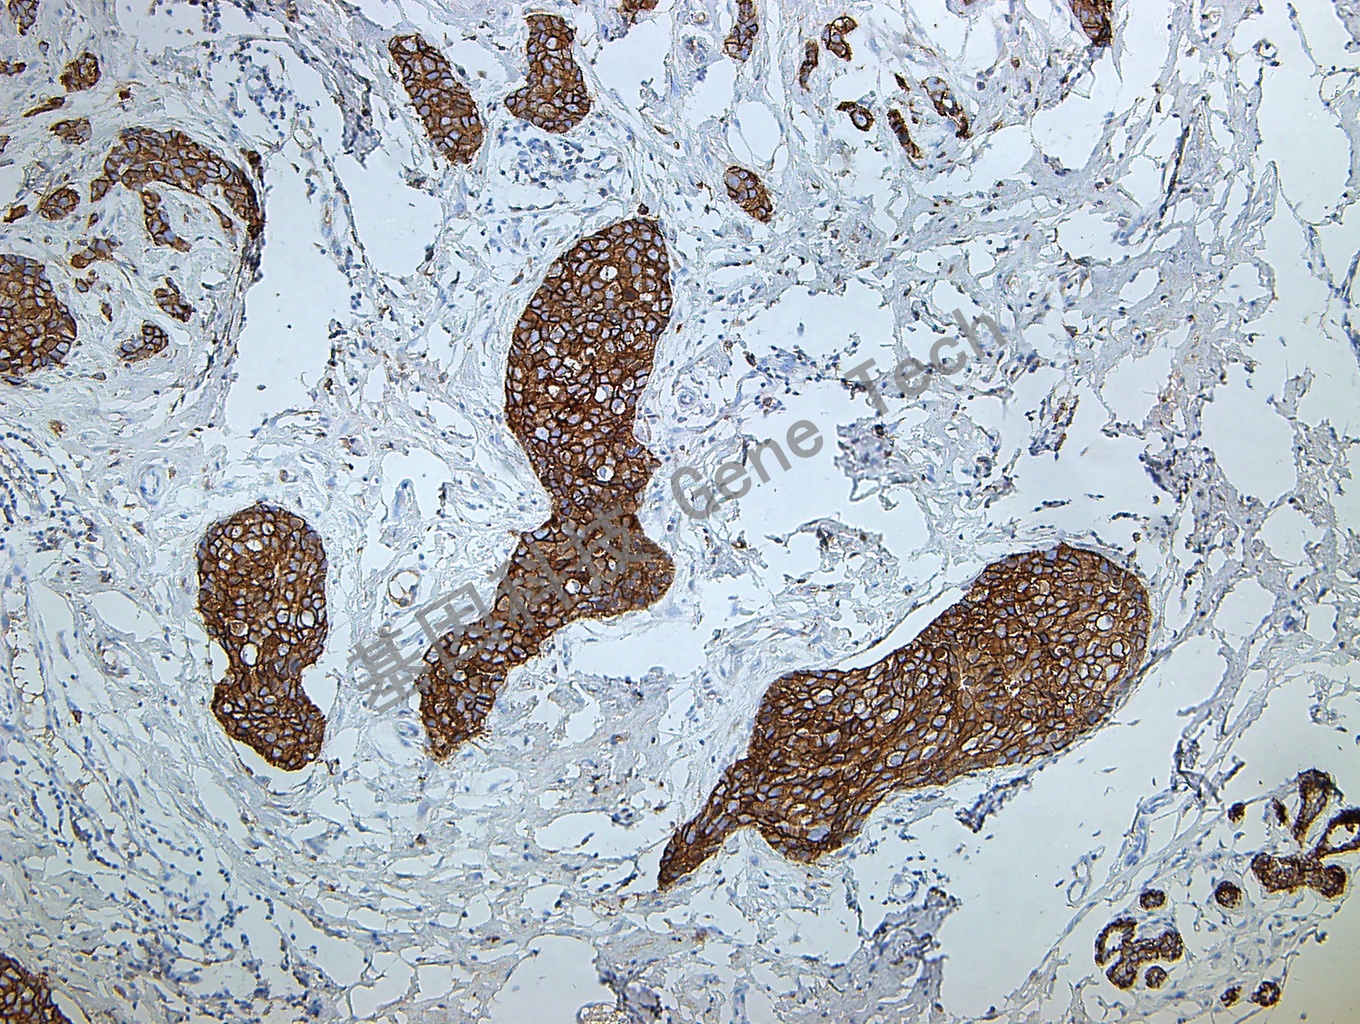

| 乳腺癌石蠟切片,用 E-Cadherin(GT2348)染色,細(xì)胞膜陽(yáng)性,DAB 顯色。 | ||

| 預(yù)處理:高pH熱修復(fù) | 陽(yáng)性部位:細(xì)胞膜 | 陽(yáng)性對(duì)照:乳腺癌/結(jié)腸 |

| 簡(jiǎn)介:E-cadherin是跨膜糖蛋白,屬于上皮細(xì)胞鈣離子依賴(lài)的粘附分子家族,在組織的生長(zhǎng)發(fā)育中發(fā)揮重要作用,其功能的降低/ 喪失可導(dǎo)致細(xì)胞連接的破壞,與腫瘤細(xì)胞的浸潤(rùn)和轉(zhuǎn)移相關(guān)。其表達(dá)與腫瘤分化程度成反比。表達(dá)的缺失與許多癌的進(jìn)展相關(guān),包括乳腺癌、膀胱癌和頭頸部鱗癌,也同肝細(xì)胞癌高級(jí)別相關(guān)。盡管此抗體上皮樣肉瘤中不表達(dá),但是若在肉瘤中表達(dá)可能同上皮樣分化相關(guān)。在滲出液中區(qū)別非腫瘤性間皮細(xì)胞和癌細(xì)胞(在滲出液中的卵巢腫瘤細(xì)胞E-cadherin 高表達(dá));在鑒別間皮瘤和其他缺少細(xì)胞粘附力的腫瘤(如:乳腺小葉癌和胃癌,這些腫瘤有著很高頻率的突變。)中有一些價(jià)值;現(xiàn)在也有報(bào)道可用于乳腺小葉癌和導(dǎo)管癌的鑒別(后者常為陽(yáng)性,前者常陰性)。 | ||